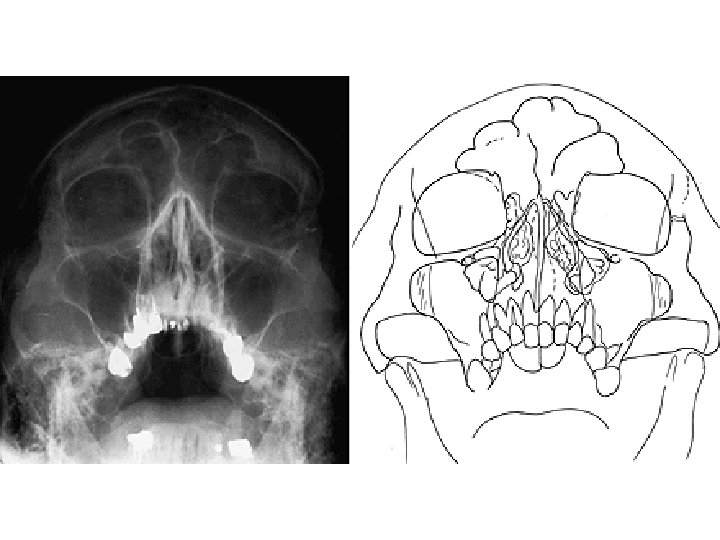

SINUS PARANASALES Sinus maxillaris Sinus frontalis Sinus ethmoidales Sinus sphenoidalis

SINUS MAXILLARIS – hiatus sinus maxillaris (Antrum of Highmore) infundibulum ethmoidale hiatus semilunaris Aa. et vv. facialis, palatina major, infraorbitalis Nll. submandibulares Nn. alveolares sup. (V 2)

SINUS FRONTALIS septum sinuum frontalium A. et v. ophthalmica V 1 Nll. submandibulares

A. et v. ethmoidalis ant. et post. A. et v. sphenopalatina V 1, V 2 Nll. submandibulares, retropharyngei SINUS ETHMOIDALES (CELLULAE ETHMOIDALES) SINUS SPHENOIDALIS septum sinuum sphenoidalium apertura sinus sphenoidalis

Meatus nasi inf. – ductus nasolacrimalis Meatus nasi medius – hiatus semilunaris – sinus maxillaris, sinus frontalis, cellulae ethmoidales anteriores et mediae Meatus nasi sup. – cellulae ethmoidales posteriores, sinus sphenoidalis